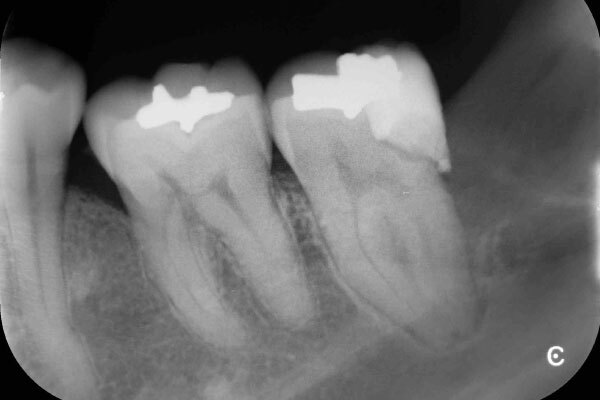

術前のデンタルX線写真と口腔内写真です。左下の一番奥の歯(#37)です。

左下の親知らずは1ヵ月ほど前に抜いたそうです。

親知らずと隣り合っていた歯の後ろ側(遠心)から虫歯が進行しています。